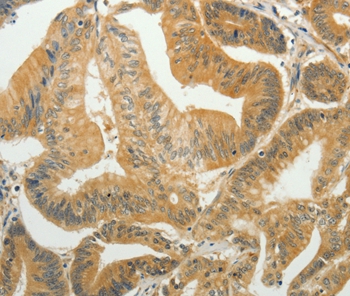

Immunohistochemical analysis of paraffin-embedded Human colon cancer tissue using #35920 at dilution 1/35.